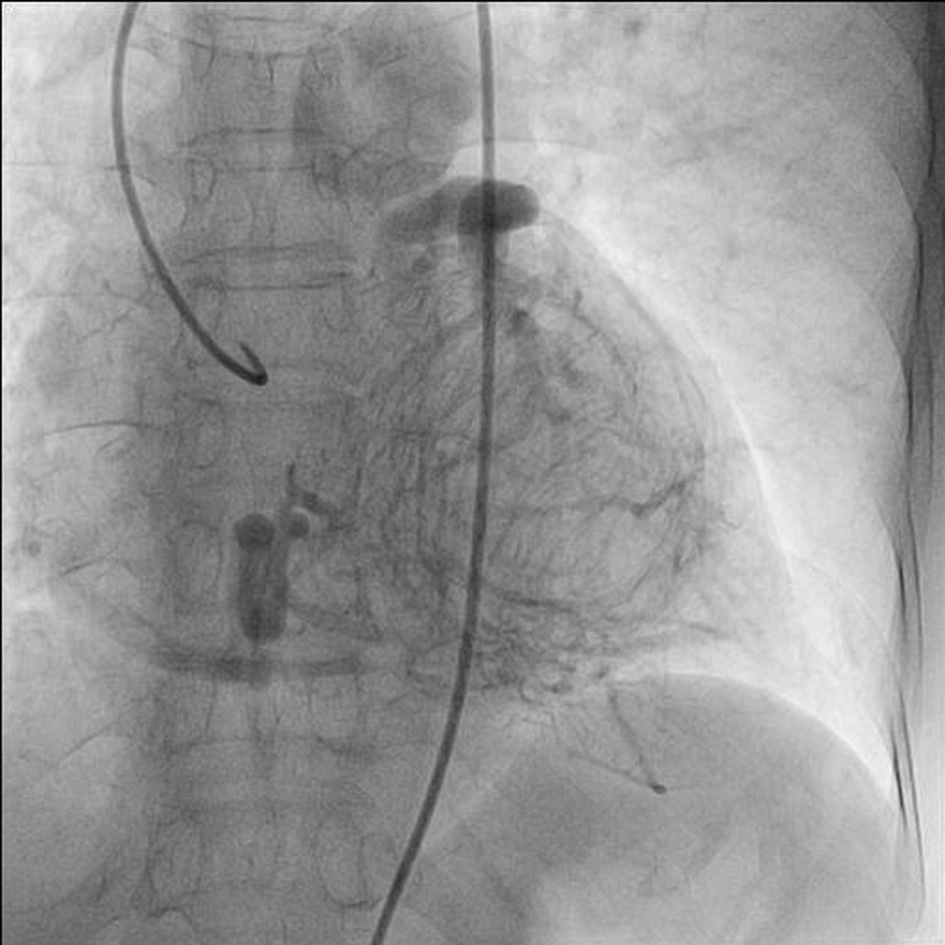

A 75-year-old woman presented with exertional angina that had progressed during previous 6 months to Canadian Cardiovascular Society functional class II at the time of admission to the hospital. Her pulse rate was 74 beat per minute and blood pressure was 152/94 mm Hg in right arm in supine position. There was no family history suggestive of coronary artery disease. Physical examination was unremarkable. On auscultation, pansystolic murmur (Levine 3/6) more prominent at the apex with radiation to axilla was heard. Mild cardiomegaly with enlargement of left ventricle and left atrium was noted on chest roentgenogram films. Electrocardiogram displayed poor R progression in precordial leads and ST-segment depression in leads V5-6, suggesting left ventricular hypertrophy. Trans-thoracic echocardiogram and color-Doppler established presence of continous flow entering the pulmonary trunk, mild mitral leak and normal systolic function (Fig. 1). Because of mild osteoarthritis of both knees, tread mill test could not be done. After proper consent, patient was taken to catheterization lab. Coronary cine-angiogram showed dilated and tortuous RCA with absence of a left coronary ostium in the left aortic sinus (Fig. 2). During the delayed phase, abundant intercoronary anastomoses (Rentrop grade 3 intercoronary collateral) were communicating with left coronary artery (Fig. 3) and still very delayed in filming sequence, retrograde flow from the left anterior descending and left circumflex coronary arteries was opacifying the left main coronary artery and its origin from the main pulmonary artery thus establishing diagnosis of ALCAPA (Fig. 4). Similar finding was recognized on reconstructed 3D coronary CT angiogram thus confirming ALCAPA (Fig. 5). Though surgical treatment by recreating a dual coronary perfusion is usually warranted regardless of the symptoms or myocardial function, it was decided not to intervene surgically as risk of cardiac surgery was outweighing the benefit. She was discharged in stable condition with medical management.

|  Click for large image | Figure 2. RAO (right anterior oblique) view of dilated and tortuous right coronary artery. |